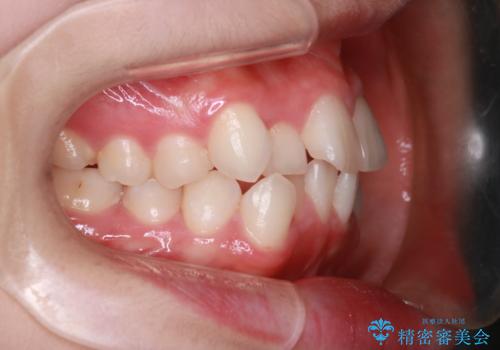

【抜歯インビザ】前歯の凸凹をなおしたい

- 前歯の凸凹を主訴に来院されました。

前歯はあまり下げる必要がなかったため、上下左右の第二小臼歯抜歯を行う治療計画としました。

途中、臼歯の近心傾斜を認めましたが、追加アライナーを使用することでリカバリーを行いながらインビザラインのみで治療を完了することができました。